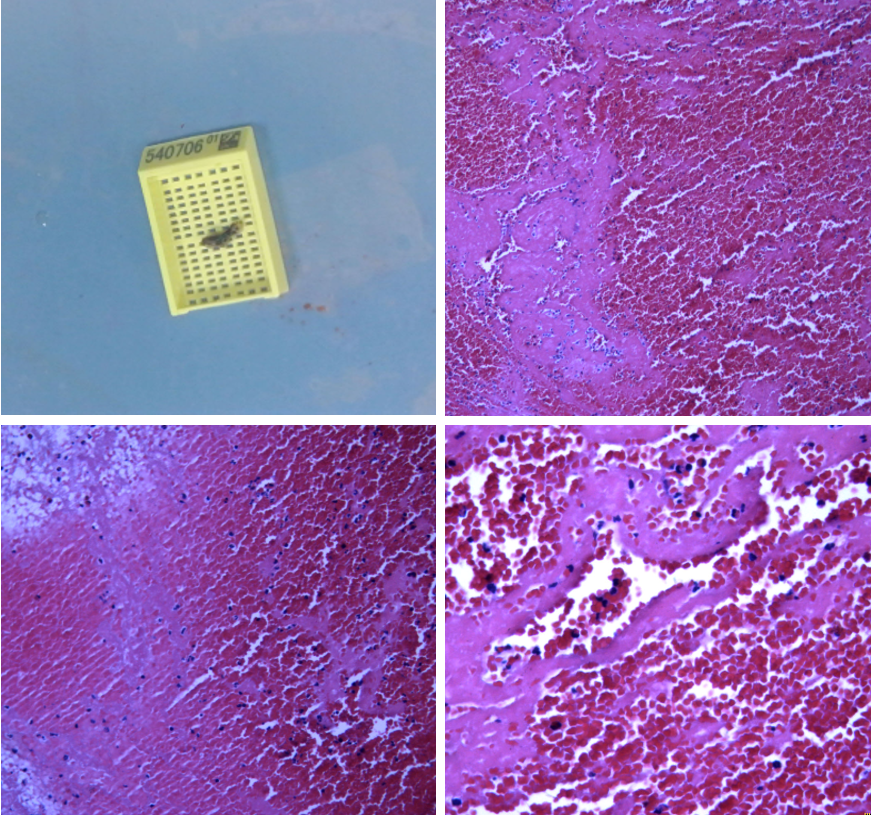

病因:心源性栓塞。

原因:血栓质韧。

该病例是心源性栓塞,血栓质韧,本例选用蛟龙4*30mm更长的取栓支架,更长长度提供更大表面积接触血栓,以独特的侧边螺旋开放结构,帮助快速高效一次三级再通。一篇研究回顾性分析了2011年6月到2017年3月使用直径4mm取栓支架及球囊指引导管作为首选治疗策略治疗ICA、MCA急性闭塞的病例。该研究中,4×30mm和 4×40mm被定义为长支架,4×20mm被定义为短支架。主要的临床结局是一次性取栓血管成功再通率(mTICI 2b/3)。研究共纳入420例患者,其中221例(53%)患者使用长支架,119例(47%)使用短支架。相对于短支架,长支架组一次性取栓血管开通率(62% vs 50%;P=0.01)和最终血管开通率(mTICI2b/3,98% vs 94%;P=0.01)更高。长支架一次性取栓成功开通率高的原因,可以从以下几方面来解释:长血栓会提供更大的表面积与取栓支架接触包裹血栓,也会在取栓过程中使张力均匀分布,在血管路径扭曲或者躁动的病人中,长支架通过增加可接受的误差范围来实现精确释放。更长的支架会增加取栓装置向血栓远端延伸的移动力,同时,在支架首个与血栓接触的网孔抓捕血栓失败的情况下,可以增加血栓取出的机会。[1]因此,通桥医疗即将上市的蛟龙4*30mm取栓支架在临床上的广泛应用值得期待。